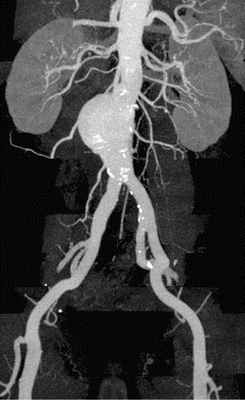

4. Ангиография (аортография) – является инвазивным методом исследования, позволяющим при помощи контраста визуализировать аорту и ее ветви. Этот метод обладает высокой диагностической ценностью, однако недостатком его является инвазивность (прокол сосуда), рентгеновское излучение, а также введение контраста, который может быть противопоказан при хронической почечной недостаточности;

5. МРТ, КТ аорты – является «золотым стандартом» диагностики аневризмы аорты и ее осложнений. Является дорогостоящим методом исследования и проводится в специализированных центрах.

Эндоваскулярное протезирование брюшного отдела аорты

Этот вид операции позволяет через два небольших разреза на бедре, под видеоконтролем, проникнуть по сосудам в аорту и заменить ее поврежденный участок изнутри. Сосудистый протез, уложенный в специальную систему, доставляется до места АА, расправляется прямо в полости аневризмы. Всю процедуру осуществляет врач-эндоваскулярный хирург под контролем рентген-установки. Таким образом, протез берет на себя силу воздействия системного артериального кровотока на слабые растянутые стенки аорты.